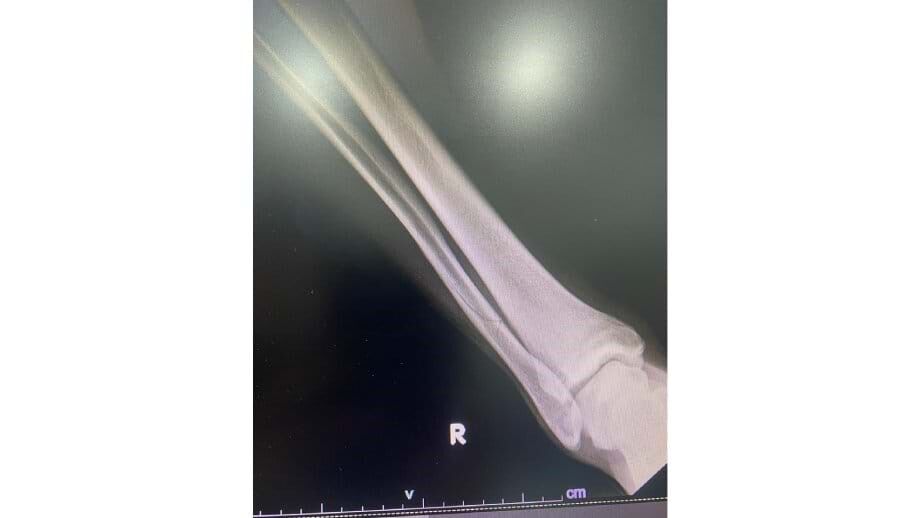

Está instalada a polémica na distrital de Lisboa. O Olivais e Moscavide denunciou, através das redes sociais, uma "entrada cobarde e assassina" de Lizinto, jogador do Tires, sobre André Frias ao minuto 90 do empate (1-1) de hoje entre as duas equipas, em jogo da 18ª jornada da 1ª Divisão da AF Lisboa. Em comunicado, o clube informou que o defesa de 30 anos contraiu "uma fratura de perónio que o irá afastar das competições no mínimo por cinco meses", publicando uma fotografia da perna e um raio-X.